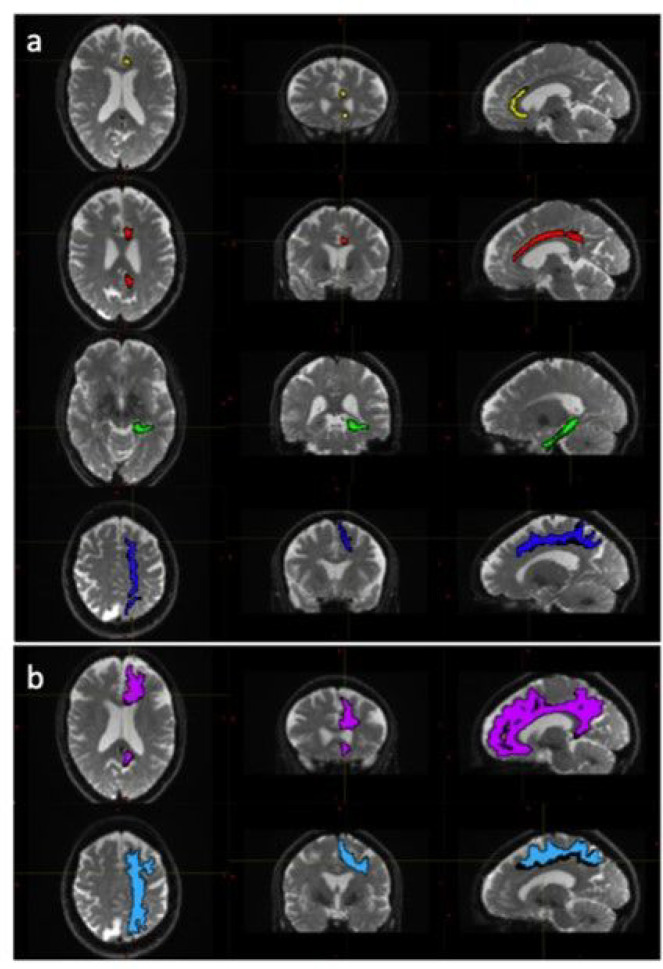

Tract Segmentation

The diffusion weighted data were processed using a combination of open-source algorithms. In brief the acquired images were denoised and the Gibbs ringing artifacts were removed using MRtrix3 (ref. Tournier, Smith et al. 2019) routines. Correction for susceptibility induced distortions, using images acquire with opposite phase polarities, motion and Eddy currents was performed employing FSL Top-up (ref. Andersson, Skare et al. 2003) and Eddy (ref. Andersson and Sotiropoulos 2016) (FMRIB Software Library, version 6.0.4; Oxford, United Kingdom). Parametric maps of mean diffusivity (MD), fractional anisotropy (FA), axial diffusivity (AD) and radial diffusivity (RD) were computed using DIPY (ref. Henriques, Correia et al. 2021) routines (https://dipy.org/) Following pre-processing of diffusion MRI scans, white matter tracts were segmented using, TractSeg (ref. Wasserthal, Neher et al. 2018). Both the 72 tracts definition included in TractSeg and the 42 tracts definition derived from Xtract (ref. Warrington, Bryant et al. 2020) were used in order to improve internal validity. Furthermore, the Xtract method divides the cingulate bundle into three distinct tracts offering a more focused analysis of white matter contiguous with the PCS. Diffusivity metrics and tract volumes were analysed in accordance with ipsilateral hemispheric PCS presence in the superior longitudinal fasciculus I (SLF-I) [both segmentation methods], the cingulum (CG) [TractSeg] and the dorsal (CBD), pre-genual (CBG), and temporal (CBT) cingulum [Xtract]. Further method description and quality control measures are documented in the Supplementary Material. Tract segmentations example are displayed in Figure 2.

Following quality control procedures segmentations were available for 125 subjects, (mean age 52.19, SD 5.12), see Table 1. The frequency of present to absent PCS was greater in the left (88/125) than right (71/125) hemisphere as expected. Individuals with a present left PCS displayed reduced FA of the left CG relative to individuals with an absent left PCS (β = −0.02, CI −0.01 – −0.0008 μm2/ms, P = 0.02). Using the Xtract method a present left PCS was associated with decreased FA in the ipsilateral CBG (β = −0.009, CI −0.04 – −0.008 μm2/ms, P = 0.002) and CBD (β = − 0.009, CI − 0.02 – − 0.0009 μm2/ms, P = 0.03) but not the CBT. These results are displayed in Fig. 5. Ipsilateral RD of the CBG was higher in individuals with a present left PCS compared to those with an absent left PCS (β = 2.22 ×10− 5, CI 7.58e-06-3.69e-05 μm2/ms, P = 0.003), see Fig. 6. Ipsilateral RD was similar according to PCS presence in the other studied tracts in both hemispheres.

Left PCS presence was associated with increased left CBG tract volume (β = 0.10, CI 0.02–0.18 μm2/ms, P = 0.012), see Fig. 7. Right PCS presence was not associated with right CBG tract volume. SLF-I, CG, CBD, or CBT tract volume were not associated with ipsilateral left or right PCS presence. Results are displayed in full in Table 3.

Results from the tract segmentation analyses indicate that absence of a left hemisphere PCS is associated with higher ipsilateral cingulate bundle FA. More specifically group diffusivity differences localise to the anterior portion of the cingulum; the peri-genual and dorsal cingulum bundles. Expectedly, no significant group diffusivity difference was observed in the offsite temporal division of the cingulate bundle. Furthermore, higher radial diffusivity and tract volume were observed in the left peri-genual cingulum bundle in individuals with a left PCS relative to those without. Ipsilateral tract volumes and diffusivity matrices were similar in the SLF-I between groups in both hemispheres. These results suggest that where a left PCS is present the ipsilateral cingulum bundle, specifically its anterior portions (peri-genual > dorsal) may display increased orientational dispersion. To the best of our knowledge these findings are novel and an association between gyrification and structural connectivity in healthy individuals has not previously been identified in the literature.